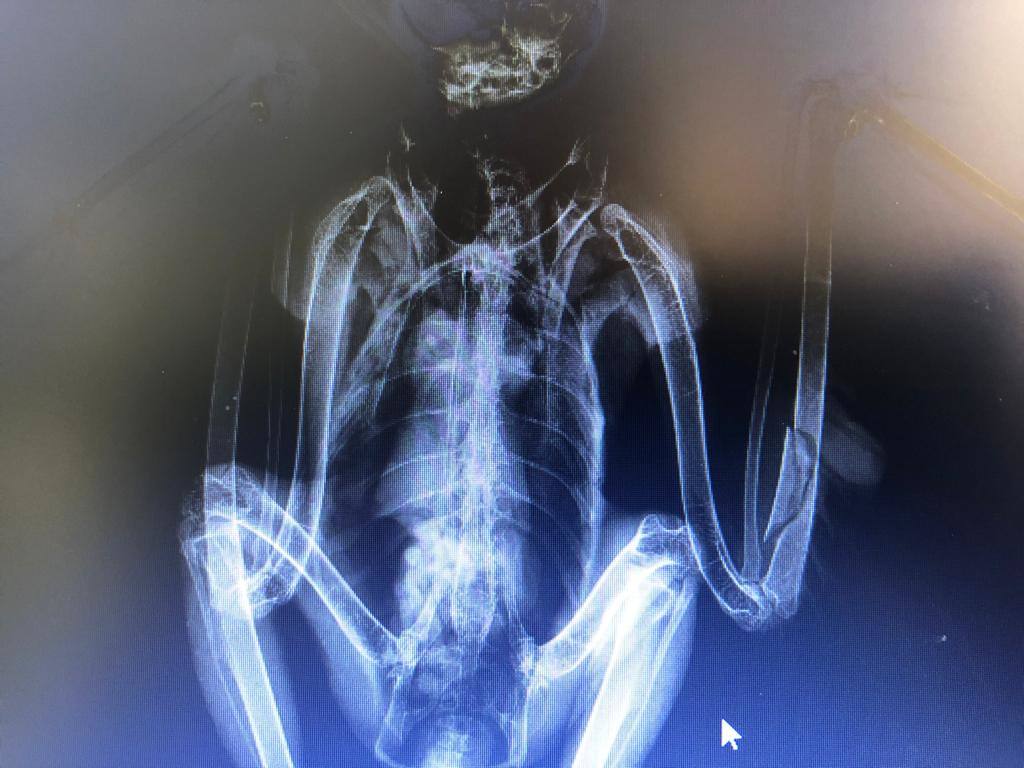

Radiografía realizada a una de las aves rescatadas

Tras dar aviso al Centro Coordinador de Operativa Insular del Cabildo (Cecopin) y a la Guardia Civil, dado que la intervención requería actuar en el arcén de una carretera, el personal del Centro de Recuperación la capturó y verificó que no podía volar. Una vez en las instalaciones de Tafira, la radiografía reveló la rotura del cúbito de una de sus alas. Los expertos barajan la posibilidad que la fractura se produjera cuando el águila intentó cazar un ratón o un lagarto, cuya abundancia en el lugar hace que acudan con frecuencia a esta zona de la Isla.